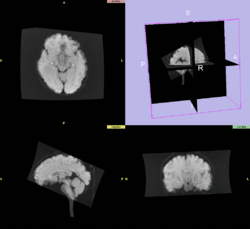

T2 to FA Affine Registration

Results using slicer2

Results using slicer3 as of 2008-04-07

• Reference 'Gold Standard'

• Slicer2 calculation using Mattes MI Affine (also uses ITK implementation)

• Result transform:

0.998582 0.0548244 0.00874164 1.86596

-0.051956 0.957673 0.0339914 -12.8223

-0.00506141 -0.00847398 0.994165 16.2862

0 0 0 1

• Software

• Slicer3 svn trunk 2008-04-07

• Parameters

• Defaults

• Method

• Use T2 as fixed, FA as moving

• Create new output transform and output volume (no input transform)

• In data module drag FA volume under the newly calculated transform

• In Transform Module select the output transform and click Invert

• Results 2008-04-07

• Output volume appears to be all 0

• Output transform looks correct, see image to the right.

0.924175 0.0524361 0.0617505 -0.457981

0.0453017 0.99089 0.0283234 -8.79902

-0.0525653 -0.0657896 1.11031 18.5389

-0 0 -0 1